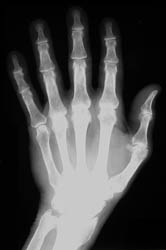

Hemochromatosis is an inherited disorder where there is increase in total iron body stores. This leads to deposition of iron in parenchymal tissues, eventually causing functional impairment. Men are affected far more frequently than in women. Arthritic changes are seen in approximately half of the patients.

Commonly affected sites of the hands include the metacarpal heads, especially at the 2nd and 3rd metacarpophalangeal joints, and the interphalangeal and carpal joints. .

Osseous eburnation, joint space narowing, well-defined subchondral cysts, radial beak-like osteophytosis at the metacarpal heads, and osteoporosis are all radiographic findings which are frequently seen in this disease process. Chondrocalcinosis is seen in up to fifty percent of the cases, with a direct correlation noted between the amount of chondrocalcinosis and the degree of arthropathy.

Soft tissues findings in the skin and hand help differentiate psoriatic arthritis from findings in hemochromatosis. There is more involvement of the distal joints in the hands with osteoarthritis. It may be difficult to differentiate hemochromatosis from rheumatoid arthritis based on radiographic findings; however, osteophytosis is rarely seen in RA. Greater propensity for the MCP joints with medial beak-like osteophytosis at the metacarpal heads and more widespread involvement of the carpal bones may help to differentiate hemochromatosis from idiopathic CPPD disease.